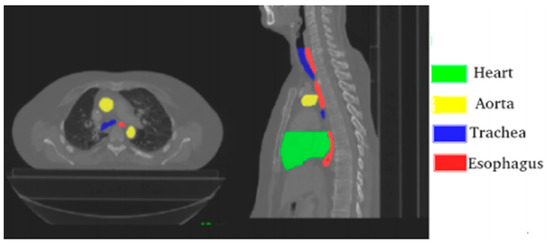

The challenge provides 40 CTs “with manual segmentation while the test set contains 20 CTs. The CT scans have 512 × 512 pixels size with in-plane resolution varying between 0.90 mm and 1.37 mm per pixel, depending on the patient. The number of slices varies from 150 to 284 with a z-resolution between 2 mm and 3.7 mm. The most frequent resolution is 0.98 × 0.98 × 2.5 mm3” [39]. Figure 1. is a visual representation of one of the CTs provided by the challenge.

Figure 1.

Axial and sagittal planes with annotated organs; source Lambert et al. [39].